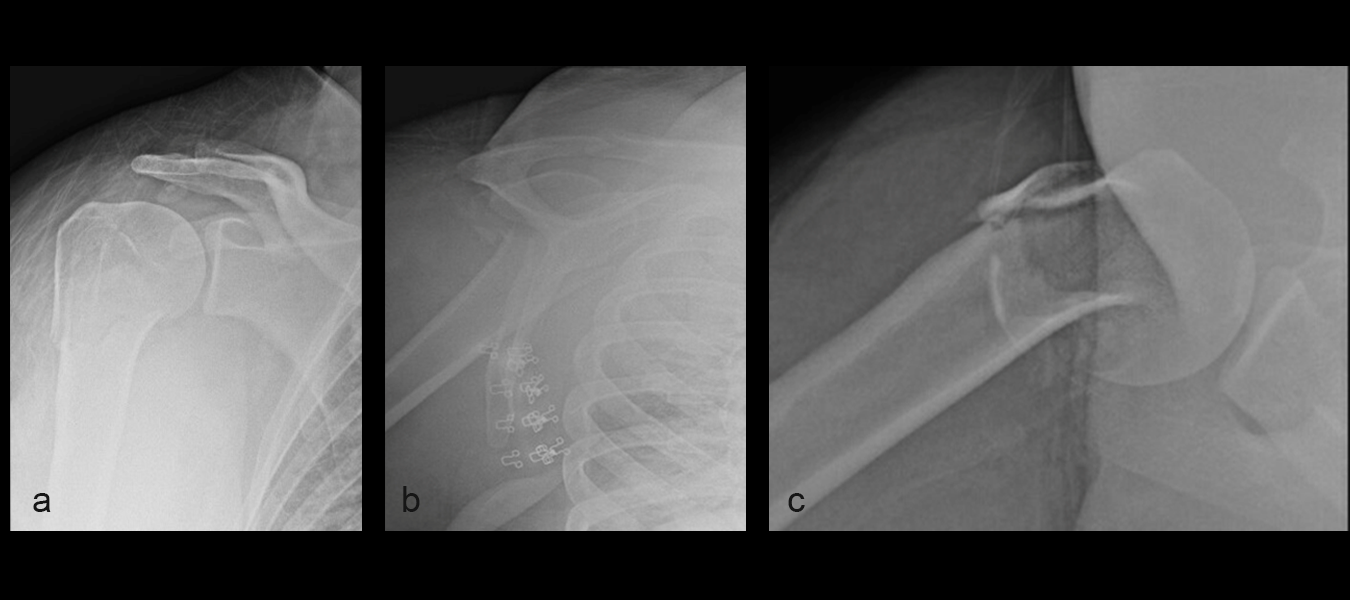

A 24-year-old woman presented to the emergency room following a motor vehicle accident. X-rays on the day of admission (Fig 1a-c) showed a fracture to the proximal humerus. There was some varus displacement of the humerus with involvement of the surgical neck and greater tuberosity.

The patient was treated with open reduction and internal fixation (ORIF). First, the fracture was reduced (Fig 2a-b). There was an attempt at closed reduction with continued displacement. Then an open reduction through a deltopectoral approach was performed. After direct reduction, a 1.6 mm K wire was placed along the anterolateral humeral surface. The provisional plate placement and reduction are depicted in Fig 3.